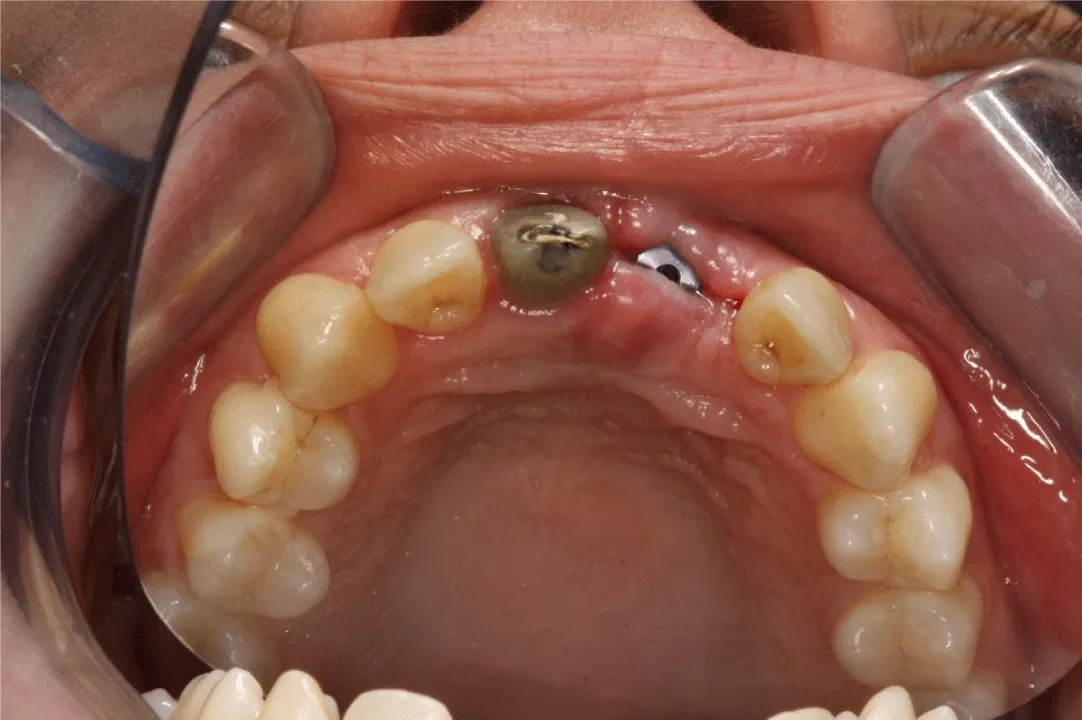

A dental clinical examination revealed good oral hygiene. After she had fallen at home, the upper left central incisor was missing (Figure 1) and the upper right incisor was abutment of an old metal-ceramic crown. The upper right central incisor was not sensitive to a cold stimulus. Options for definitive prosthetic rehabilitation were discussed with the periodontist and explained thoroughly to the patient, including removable prosthesis, fixed partial denture, or a fixed implant prosthesis. Because of her age and due to her esthetic problem, the classic, conservative prosthodontic treatment of an early insertion of a dental implant, a maxillary implant fixed crown/Fixed Partial Denture (FPD), and one conventional single crown/Fixed Partial Denture (FPD) were planned as a treatment to restore occlusion and esthetics.

The best option to save an avulsed tooth is an immediate re-implantation [28]. However, this was not possible for this musician. An appropriate emergency treatment was provided. Early insertion of an implant fixture was selected because of the need to prevent excessive bone resorption and deformation of the alveolar ridge. A removable prosthesis was used for a provisional restoration, consisting of two artificial teeth, an acrylic base, and two wire clasps on both intact second premolars. This acrylic provisional superstructure was inserted, tried, and adjusted in the clinic, considering tonguing or embouchure (Figure 2). A cantilever restoration was considered ineffective due to the condition of the neighboring teeth and the risk of extensive forces on the restoration while playing the clarinet. The patient was advised to start with easy practice and playing and she made an early return to music even with the provisional removable prosthesis. When it was tried, the acrylic base on the palate was reduced according to performance and patient preference.

Two weeks later, a titanium dental implant (Brånemark System Mk III RP 3.75×18mm, Nobel Biocare, Gothenburg, Sweden) was placed in the position of the missing left central incisor (Figure 3). The implant achieved bicortical anchorage with adequate primary stability.